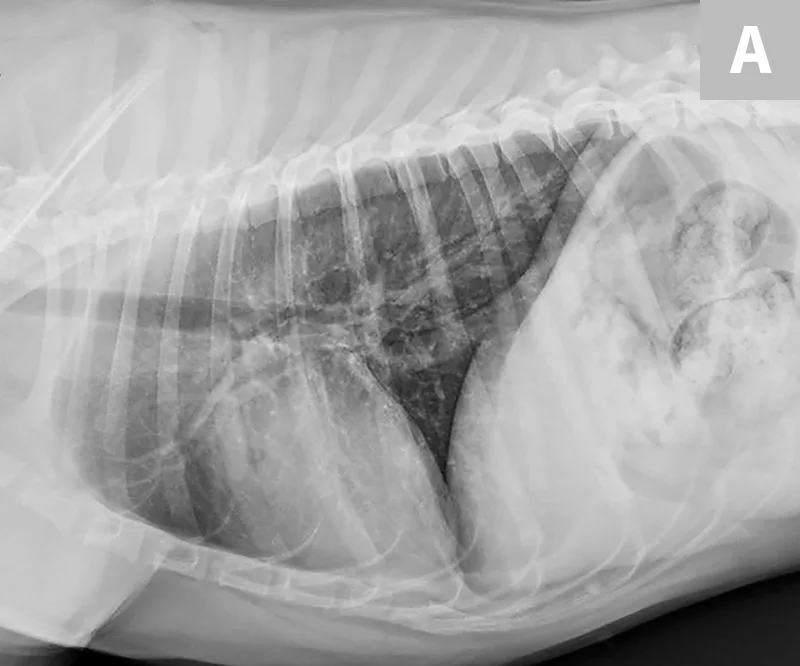

Thoracic radiograph of dog with lung and cardiac changes due to severe heartworm disease.

Radiograph from a dog with severe heartworm disease illustrating severe pulmonary arterial dilation, right heart enlargement, diffuse bronchointerstitial infiltrate, and focal region of pulmonary consolidation from embolized heartworms

Radiographs before (A) and 11 days after (B) melarsomine injection showing increased overall pulmonary infiltrate with focal region of pulmonary consolidation from embolized worms (black arrow). A progressive increase in cranial pulmonary artery size can be seen (gray arrow). Images courtesy of Clarke E. Atkins, DVM, DACVIM